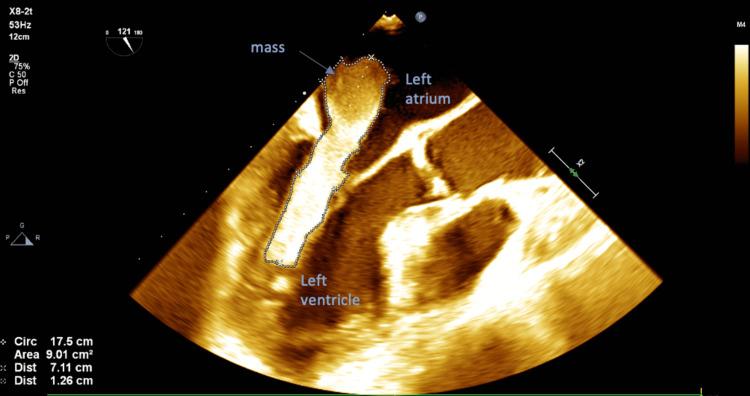

A 75-year-old Caucasian female with a past medical history including insulin-dependent diabetes mellitus, hypertension, and dyslipidemia, presented to the emergency room for having palpitations for three weeks. Echocardiography revealed a very large left atrial mass mimicking myxoma. Mass was excised and examined by pathology, revealing a mural thrombus. A mural thrombus is not an uncommon mass found in the left atrium. However, it does not often present symptomatically, strongly mimics an atrial myxoma on cardiac imaging, and has rarely ever been reported to be greater than seven centimeters in any dimension. We present a case of a 75-year-old Caucasian woman with a massive, symptomatic cardiac thrombus masquerading as a myxoma on imaging.

一名75岁的白种女性,既往有胰岛素依赖型糖尿病、高血压和血脂异常病史,因心悸三周就诊于急诊室。超声心动图显示左心房有一个非常大的肿块,类似黏液瘤。肿块被切除并送病理检查,结果显示为壁血栓。壁血栓在左心房并不罕见。然而,它通常没有症状,在心脏成像上与心房黏液瘤极为相似,而且从未有过任何维度大于7厘米的报道。我们报告一例75岁白种女性病例,其心脏有一个巨大的、有症状的血栓,在影像学上伪装成黏液瘤。